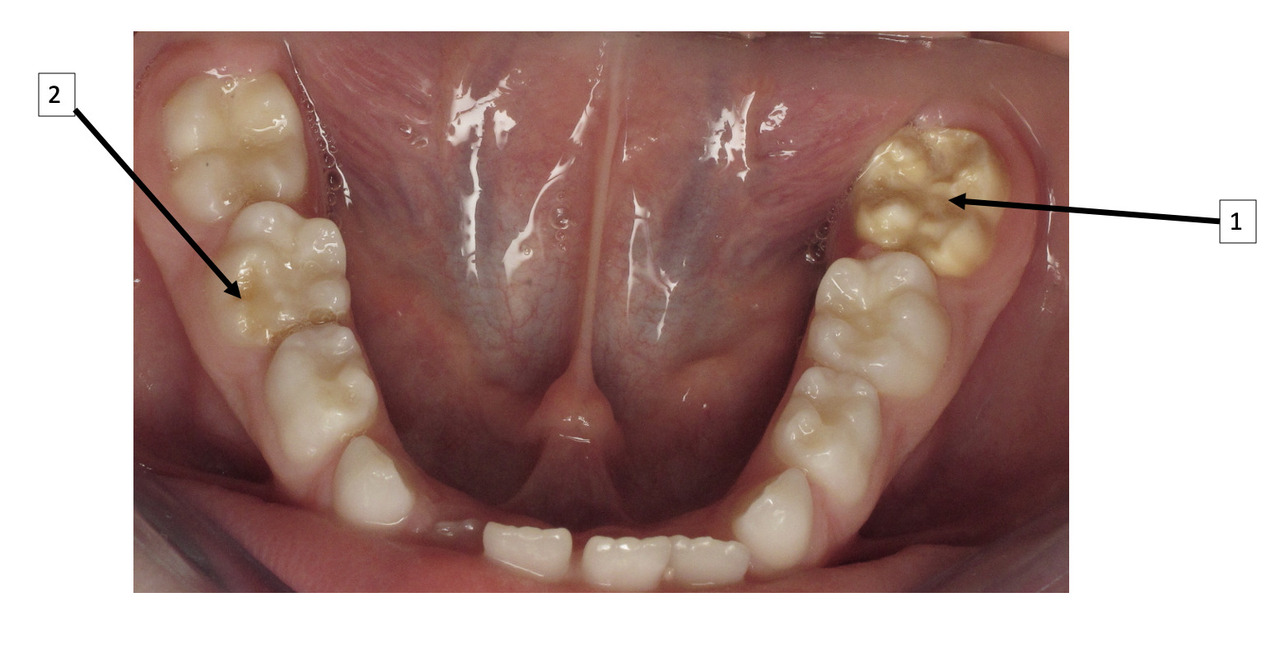

La MIH est une anomalie de la structure de l’émail se traduisant par un défaut qualitatif de l’émail sur au moins une des quatre premières molaires permanentes, associé ou non à une atteinte d’une ou plusieurs incisives permanentes (fig. 1).1 Les autres dents permanentes sont plus rarement atteintes. On peut également retrouver une atteinte similaire au niveau des deuxièmes molaires temporaires, appelée alors HSPM (hypomineralised second primary molar). Un enfant atteint de HSPM a cinq fois plus de risque d’être atteint de MIH en dentition permanente.

Le diagnostic repose sur l’observation clinique : des opacités (taches) blanches, beiges ou brunes de taille variable sont présentes et visibles sur les dents atteintes (fig. 1, 2 et 3). Les opacités, bien démarquées, sont présentes dès l’éruption de la dent et leur taille ne se modifie pas dans le temps. Cependant, l’émail étant plus fragile, des fractures amélaires post-éruptives sont observées, entraînant des pertes de substance surtout au niveau des molaires qui sont soumises aux forces de mastication. L’atteinte est asymétrique, c’est-à-dire que pour un même patient sa sévérité peut varier d’une dent à l’autre, allant d’une absence d’atteinte à une perte de substance importante, en passant par une dyschromie discrète. Si une tache est observée sur une incisive permanente, il est important d’examiner les molaires permanentes. Le médecin généraliste doit alors évoquer une anomalie de structure dentaire et orienter le patient vers un chirurgien-dentiste. Celui-ci confirmera le diagnostic de MIH ou établira un autre diagnostic. Les diagnostics différentiels sont :